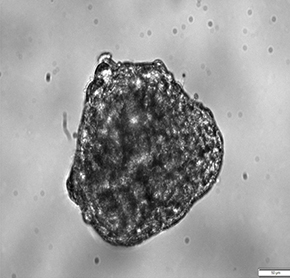

肿瘤类器官药敏是人医个性化医疗的最新诊断方式,模拟治疗药品进入肿瘤微环境内在空间不同部位毒杀肿瘤的效果。

· 肿瘤类器官模拟肿瘤真实且复杂的生物特性